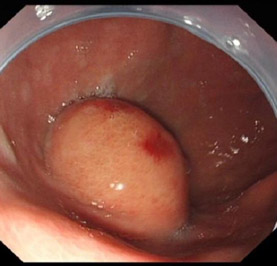

1、胃镜和超声胃镜检查:胃镜检查,可以明确病变位置、形状、数目、大小,有无溃疡及出血;常见的胃镜表现如下图,一般是胃粘膜下光滑隆起性病灶。粘膜是光滑的,少数会有小的溃疡,有时会有血茄附在上面,这是与胃癌区别的重要因素,胃癌都是起于胃粘膜,可以看到粘膜的溃烂,粘膜不会是光滑的。胃镜下如果考虑是间质瘤,一般会加做超声胃镜。目前超声内镜(EUS) 是监测黏膜下肿瘤的首选方法,可清晰显示病变来源与胃壁各层结构,部位以及病变的大小,形状,边缘和回声等情况。同时,如果考虑是胃间质瘤,一般不取活检病理。一是不容易取到间质瘤组织,在粘膜下方,二是容易导致肿瘤破裂,导致扩散。除非肿瘤巨大或侵犯周围脏器,直接手术切除有困难需要术前服药治疗,必须取活检外,其余不建议取病理活检。

胃镜下表现,粘膜光滑,病变位于粘膜下